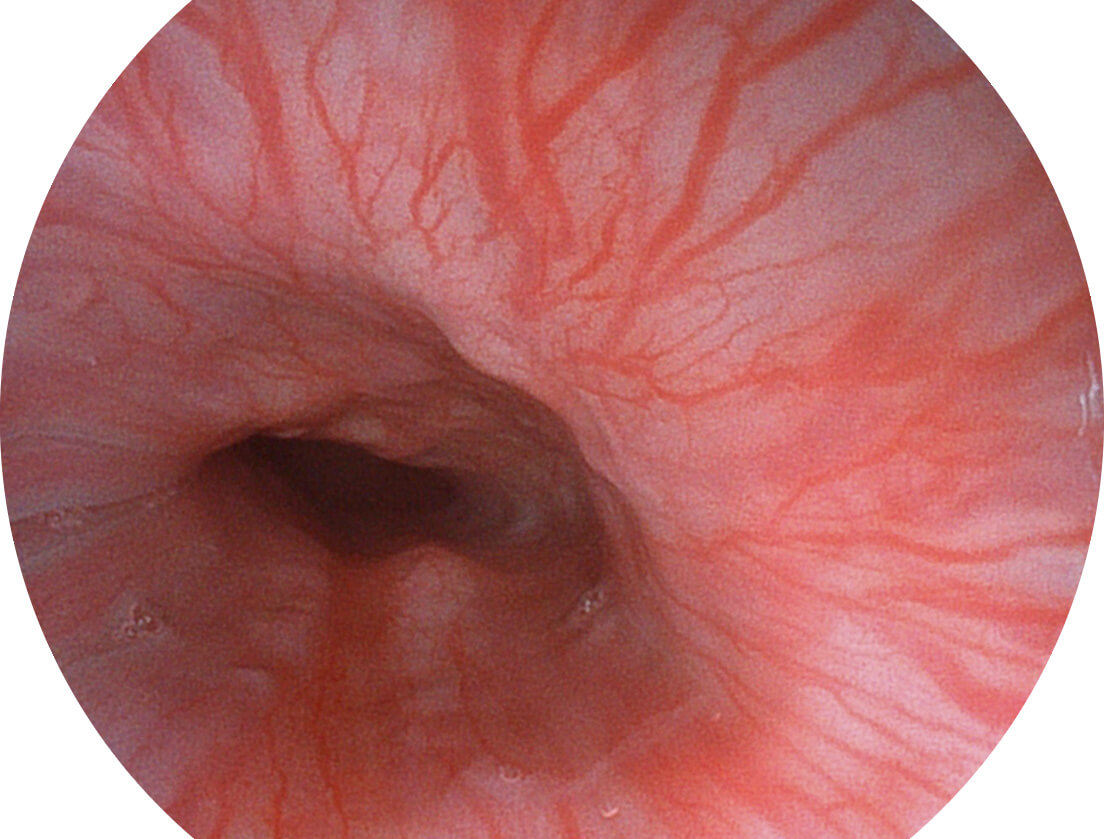

強(qiáng)調(diào)淺層黏膜結(jié)構(gòu)的同時(shí),保證照明亮度和提升淺層微血管與中層血管顏色對比度,病變邊界更清晰。

• 白光圖像 VIST圖像